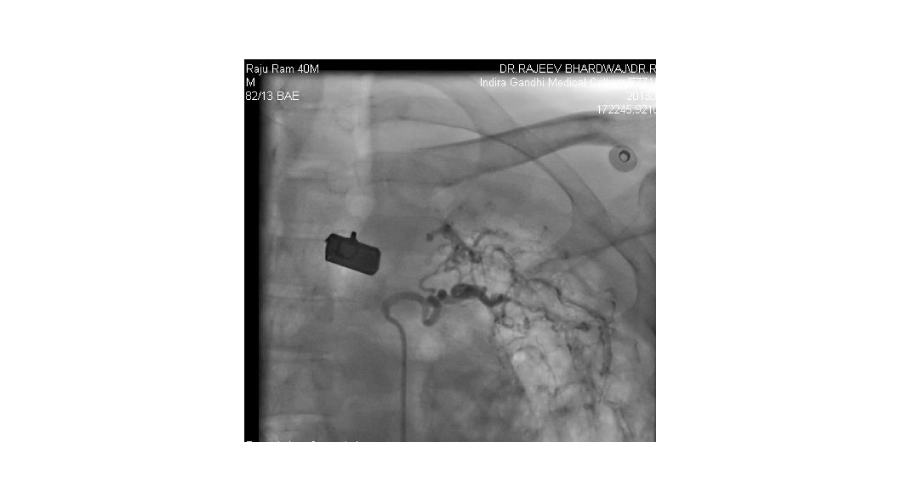

Patients admitted with moderate to severe hemoptysis in pulmonary medicine or general medicine department were the subjects of study. The patients were subjected to routine blood examination, X ray of chest, and CT scan of chest (Except in emergent situation). If required, bronchoscopy was done to localize the side of bleeding and for diagnostic purposes. Informed consent was taken from all patients. Commonest approach was from right femoral artery puncture. Seven French sheath was inserted in the femoral artery with the help of Seldienger technique. According to the protocol, bronchial arteries, intercostal arteries, subclavial arteries and its branches including the internal mammary arteries were selectively hooked with a catheter and contrast was injected into these arteries to see for the signs of bleeding. Initial attempt was made to see for bleeding source on the side suggested by X-ray or CT scan or bronchoscopy. Before the completion of procedure, vessels of other side were screened. If no bleeding vessel was found after screening on both sides, pulmonary arteriography was done with pig tail catheter to see for the source of bleeding from pulmonary artery. An artery was considered abnormal/ potential bleeder, if extravasation of contrast, aneurysm, increased caliber with tortuosity, vascular tufts, arterio-arterial or arterio-venous fistulas were seen. Once diseased artery was identified, it was selectively cannulated with a catheter. Most commonly used catheters were right Judikin, Cobra I, and Simmon I. The vessels were hooked deeply with the catheter, with the support of .018 inch guide wire. The vessel was then embolized with poly vinyl alcohol (PVA) particles mixed with contrast agent. The particles were injected till vessel was occluded or reflux of contrast was seen. If a vessel could not be hooked deeply, a micro-catheter was passed through the catheter and PVA particles were injected through micro-catheter. Size of particles used was 500-700 microns. If it was difficult to cannulate the branches of subclavian artery selectively, due to fibrosis, the artery was approached from radial artery puncture. Criteria used for successful embolization was that all diseased arteries were embolized. If spinal artery was seen on cannulation of a bronchial artery, the embolization was done distal to its origin to avoid inadvertent embolization of spinal artery.

We found that most of the cases required embolization of multiple vessels. In around half of the patients, both bronchial and systemic vessels required embolization. In around one fourth of patients, only bronchial and in another one fourth, only systemic vessels were the source of bleeding. In contrast to other studies, out of 192 vessels embolized, around 37% vessels were arising from subclavian arteries, (including 10% internal mammary arteries) and in 27% intercoastal arteries were the source of bleeding. Swansen et al., embolized the following arteries: right bronchial artery (34), left bronchial artery (11); combined right and left bronchial trunk (9); intercostal arteries (45); right internal mammary artery (8); left internal mammary artery (8); inferior phrenic artery (10); lateral thoracic arteries (3); thyrocervical trunk (2); and a left gastric artery (1) [11]. The complications of BAE in this study included subintimal dissection in two patients (4%), arterial perforation by a guide wire in one patient (2%), and reflux of embolic material into the aorta without adverse sequelae in one patient (2%). Pleuritic chest pain post procedure occurred in two patients (4%), shoulder pain post procedure in one patient (2%), and transient dysphagia in one patient (2%). One patient developed a groin hematoma at the puncture site.(Figures 1-5)